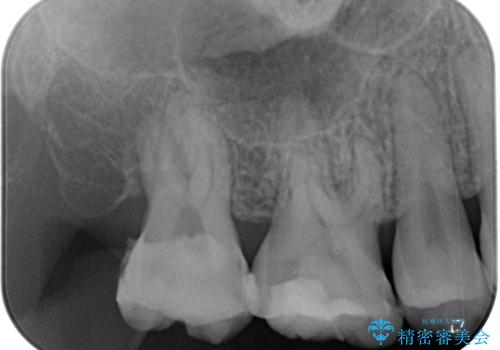

下顎大臼歯は根管治療がされている歯が咬合時に痛みを感じ、上顎の大臼歯2歯は冷たいものがしみる状態でした。

根管治療を行った歯の周辺にある病変は数ヶ月後にレントゲン写真を撮って確認する必要があるため、今後経過観察を行っていく予定です。